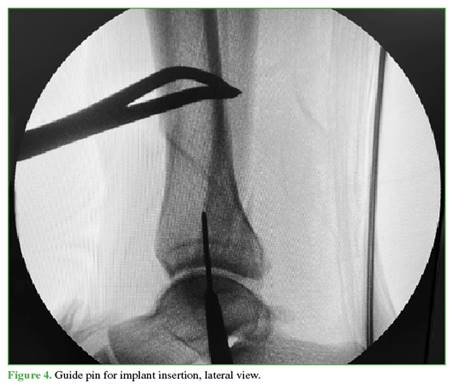

A 3 cm incision is then made distally from the tip of the tibial malleolus (Figure 2). Using a guidewire, the entry point is identified in the center of the tibial malleolus in both planes (Figures 3 and 4), and then enlarged with a cannulated reamer (Figure 5). An olive-tipped guidewire is inserted (Figure 6), and reaming of the medullary canal is performed through a soft tissue protector (Figure 7).